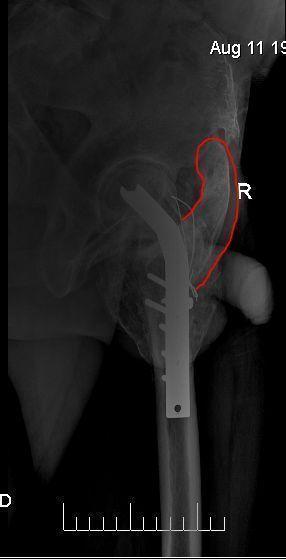

[Ortho] Неправильное сращение чрезвертельного перелома, перелом конструкций и оссификат

Вложение не в текстовом формате было извлечено…

Имя     : ЖПТХН.jpg